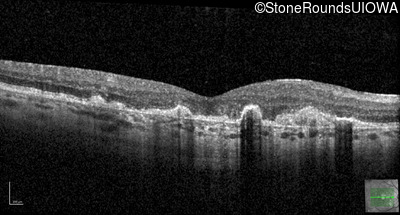

Malattia Leventinese (IIJ)

Malattia Leventinese (IIJ)

This 43 year old woman has experienced a gradual reduction in her central vision for the past 3 years.

| Malattia Leventinese | EFEMP1 | Arg345Trp CGG>TGG | AD |